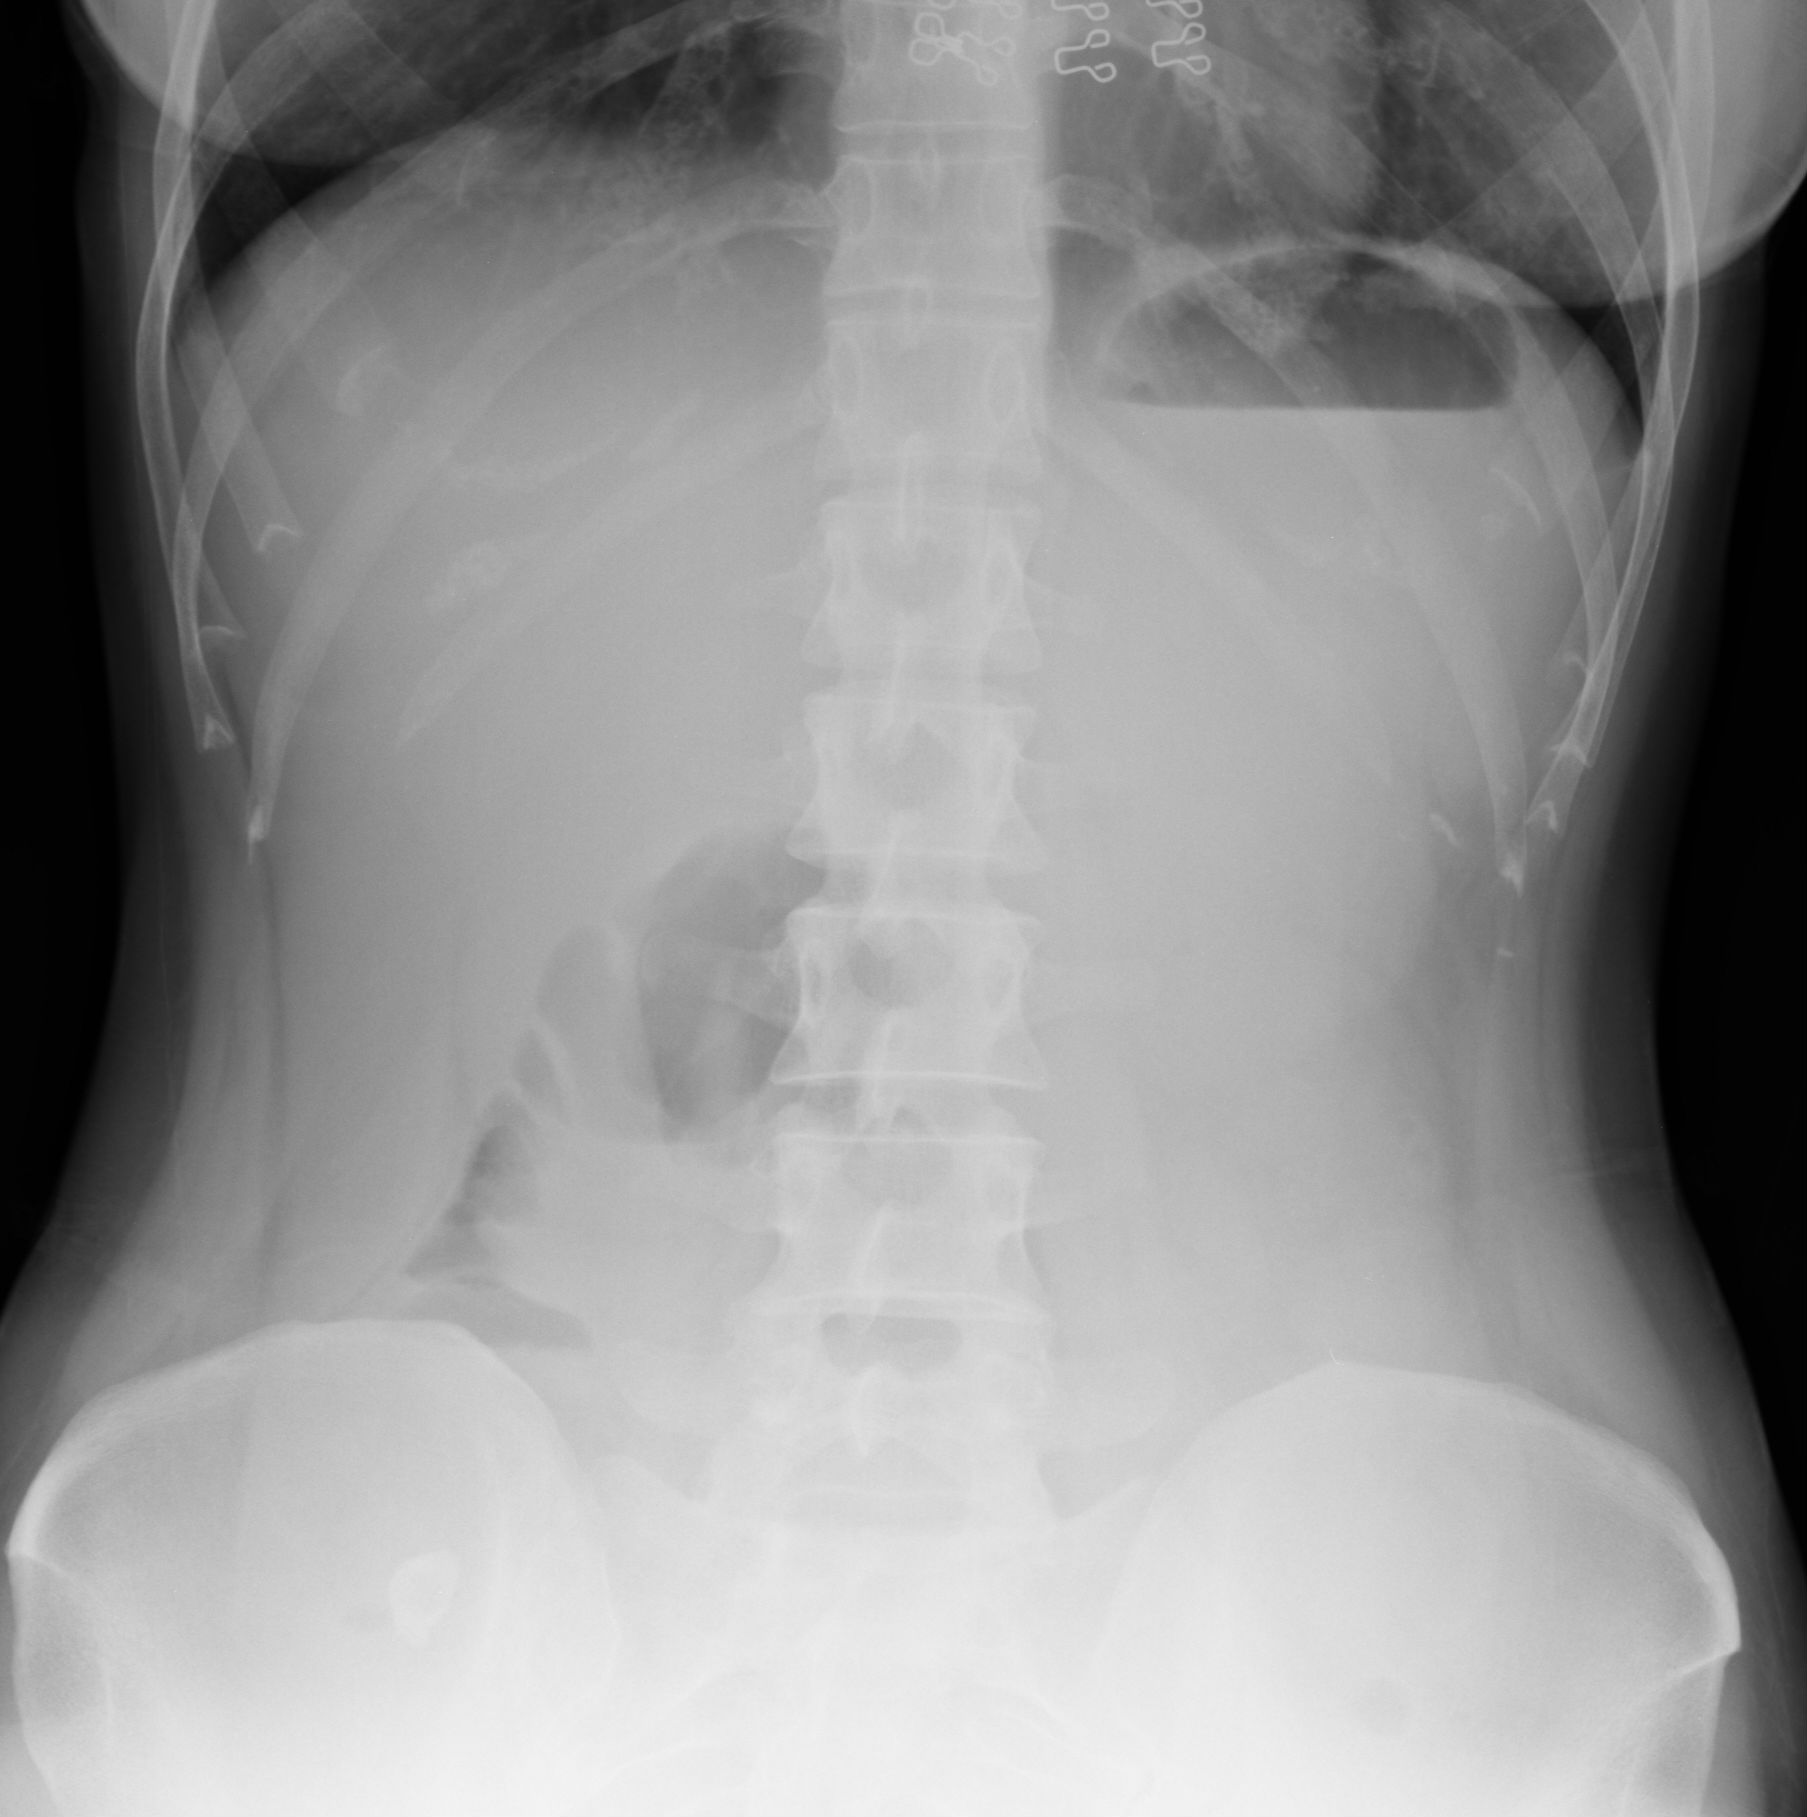

Нормы обзорной рентгенографии брюшной полости